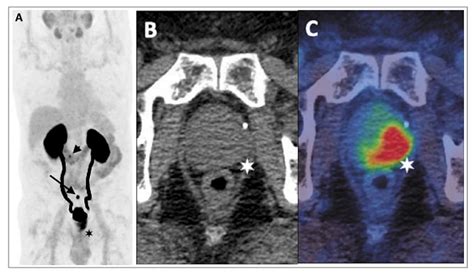

The diagnostic process typically involves three specific sequences that make up the "multi-parametric" aspect of the scan:

• T2-Weighted Imaging: Provides high-resolution anatomical details of the prostate structure.

• Diffusion-Weighted Imaging (DWI): Measures the movement of water molecules in the tissue, which is often restricted in malignant tumors.

• Dynamic Contrast-Enhanced (DCE) Imaging: Monitors how a contrast agent flows into the tissue, helping to highlight areas with abnormal blood vessel growth typical of cancer.

The PI-RADS Scoring System

To standardize the interpretation of MRI results, radiologists utilize the Prostate Imaging-Reporting and Data System (PI-RADS). This scoring system ranges from 1 to 5, helping urologists determine the likelihood of clinically significant cancer:

• PI-RADS 4: High probability of significant cancer.

• PI-RADS 5: Very high probability of significant cancer.